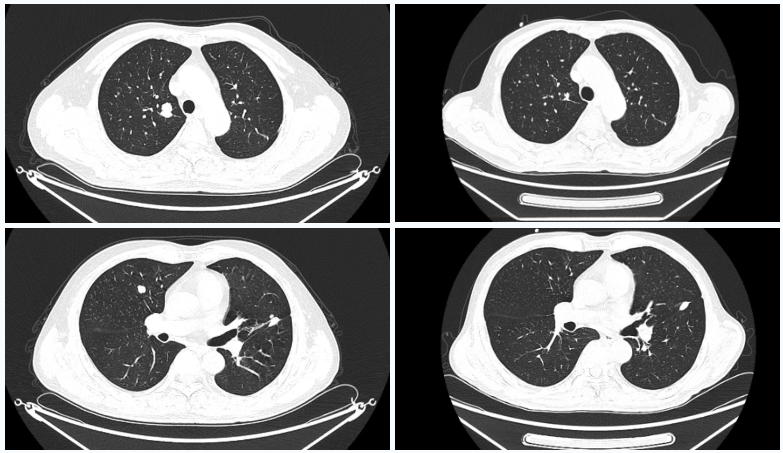

△2025年8月疗效评估时患者CT检查(右)较基线(左)对比

△2023年2月患者基线时CT(左)与2024年4月时CT(右)检查所见对比

患者2025-02-13起转为呋喹替尼单药治疗,剂量及用法同前,共治疗9个周期,后患者于2025-08-21复查CT及SPECT骨扫描,靶病灶疗效评价仍维持PR,但检查同时示胸12椎体存在转移可能,综合考虑疗效为疾病进展(PD),遂终止呋喹替尼治疗。